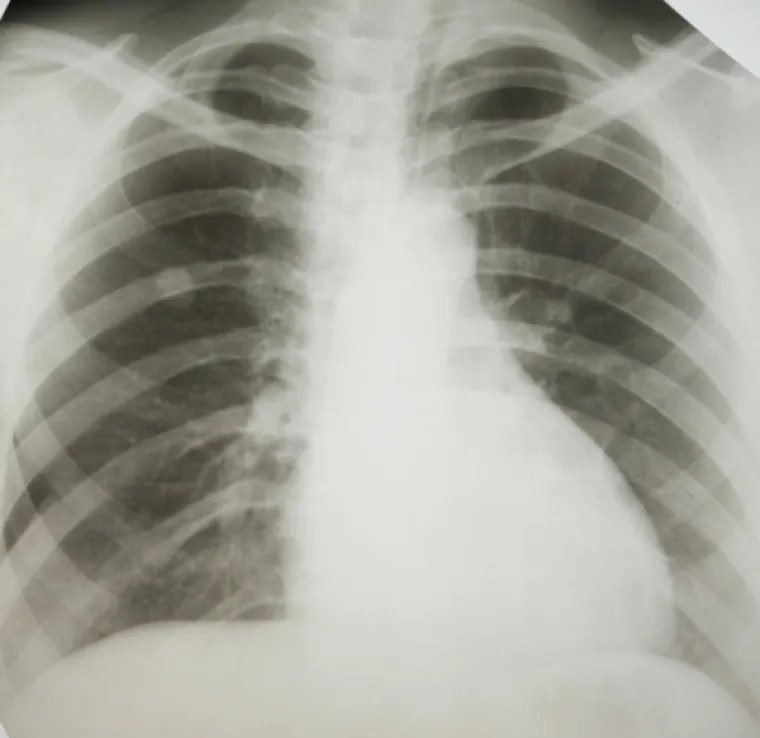

Marihuana je lijek, ali i mogući uzrok bolesti: evo gdje pomaže, a gdje odmaže

O marihuani kao lijeku i dalje se lome koplja, iako ljudi već 3000 godina liječe bolesti ovom biljkom. U posljednje vrijeme sve više zemalja legalizira marihuanu u zdravstevne svrhe, no i dalje nema dovoljno dokaza koje joj idu u prilog. Evo koje su medicinske dobrobiti marihuane, a kod čega ne pomaže ili čak radi i veliku štetu za zdravlje